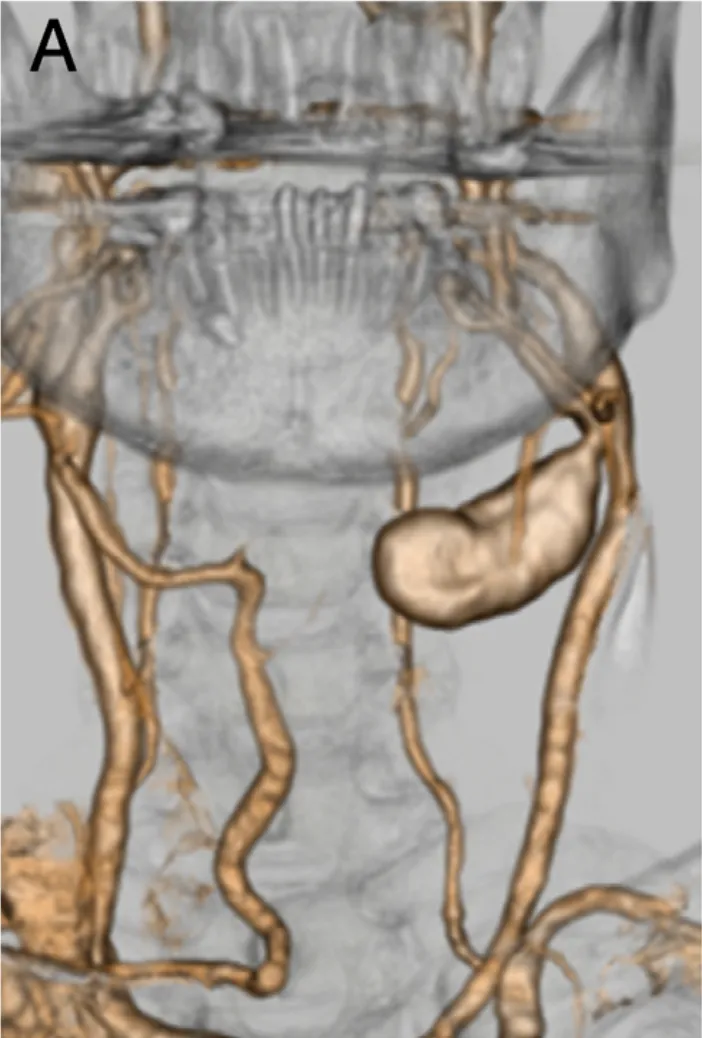

当体检报告上出现左侧后交通动脉瘤时,这位定期体检的养生达人怎么也没想到,这个直径仅12毫米的血管异常,竟会在两年间疯长至35毫米,并且右边身体开始僵硬、眼前开始模糊,还有意识...